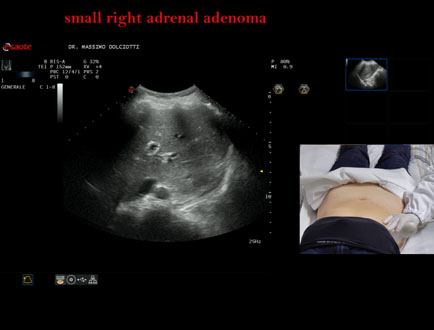

Data inserimento: 06/11/2025

Ecografia del: 31/10/2025

Strumento: Esaote MyLab Eight

Sonda: Convex Multifrequenza 1-8 MHz

Età Paziente: F 69 anni

Motivazione dell'esame: follow up per piccolo adenoma surrenalico.

Commento all'esame: le immagini ed il video documentano in sede surrenalica destra, formazione ipoecogena, a margini definiti, rotondeggiante, delle dimensioni di 15,8 x 14,8 mm, da ricondurre ad adenoma surrenalico.

Conclusioni: piccolo adenoma surrenalico destro (small right adrenal adenoma).